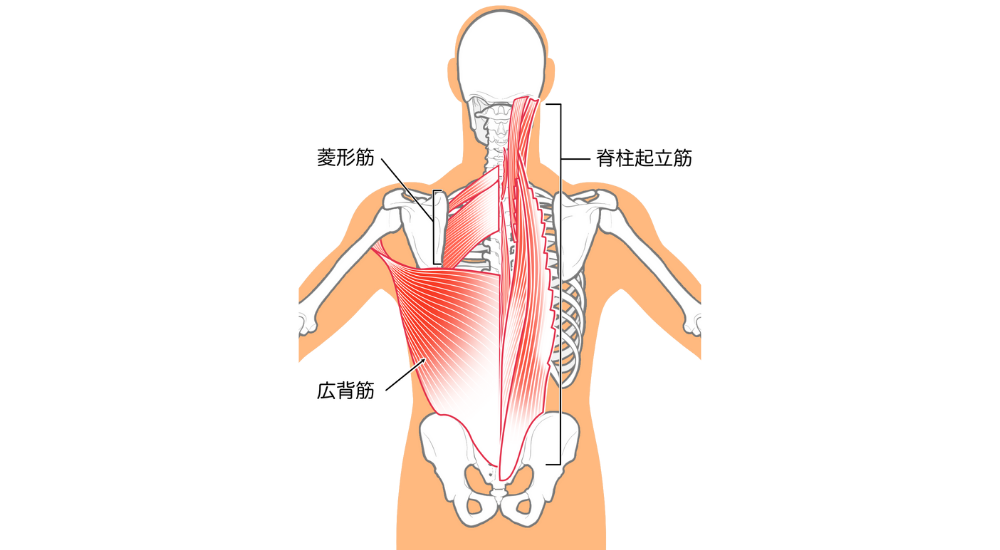

- 菱形筋: 肩甲骨と背骨の間。猫背で引き伸ばされて硬くなり、肩甲骨内側の凝りや痛みの原因となります。

- 脊柱起立筋(特に胸部): 背骨に沿った筋肉。猫背で引き伸ばされて硬くなり、背中の張りや痛みの原因となります。

- 脊柱起立筋(特に腰部): 腰の背骨に沿った筋肉。反り腰で常に緊張・短縮しやすく、腰痛の大きな原因となります。